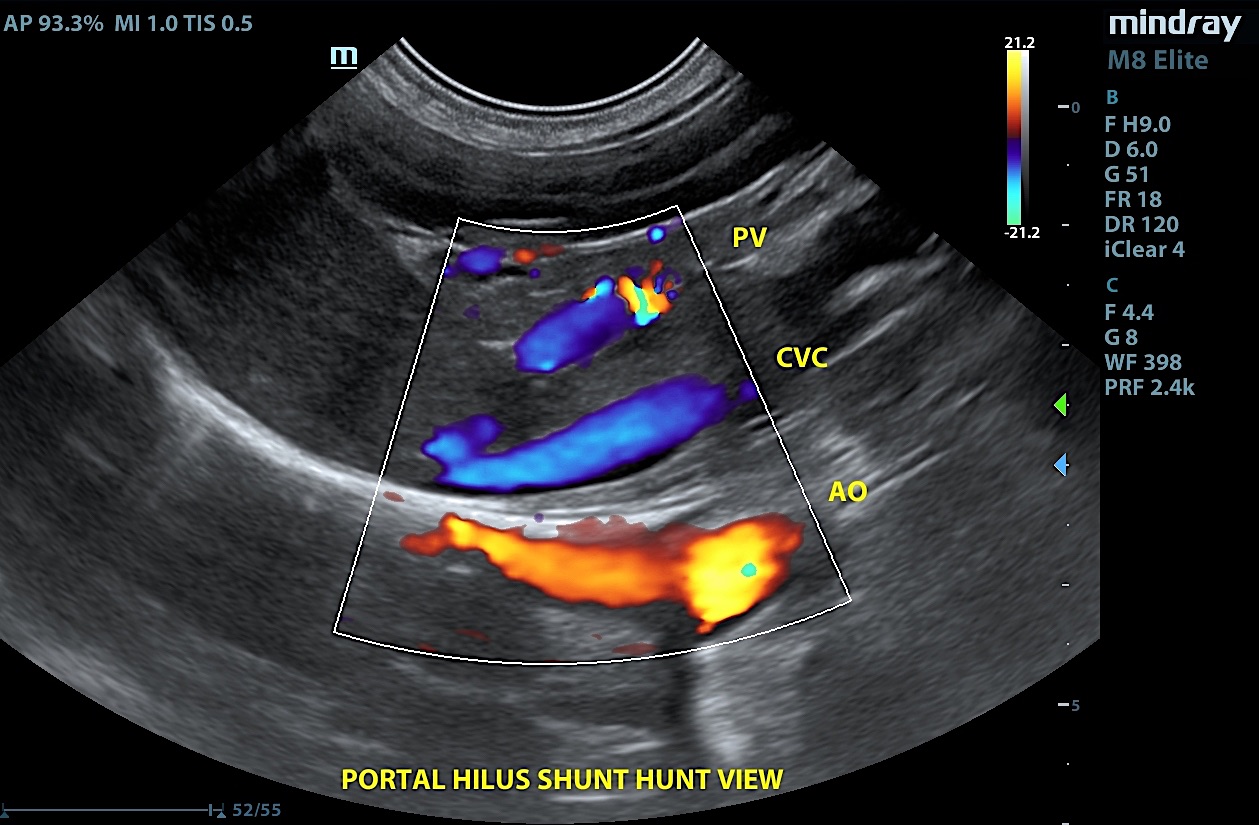

Our experienced SDEP® certified technicians, Kelly Reschny, RVT & Crystal Hill, RVT will come to your clinic and perform a diagnostic ultrasound on your patient. The images will then be submitted to a SonoPath specialist who will provide a comprehensive report. The report will include sonographic findings, internal medicine diagnostics and treatment recommendations with annotated images identifying any pathology or areas of concern. If needed, our technicians can perform ultrasound-guided fine needle aspirates, abdominocentesis or pericardiocentesis.

The Focal Zone fueled by Sonopath, a mobile veterinary ultrasound service, gives you a sneak peek on its monthly Star Cases.

VSD, CHF, and Thoracic Mass In A 4-Year-Old Intact Male Sphynx Cat: Our 2023 Star…

Retrobulbar Mass – Right Eye In A 4-Year-Old, MN, English Setter: Our 2023 Star Cases